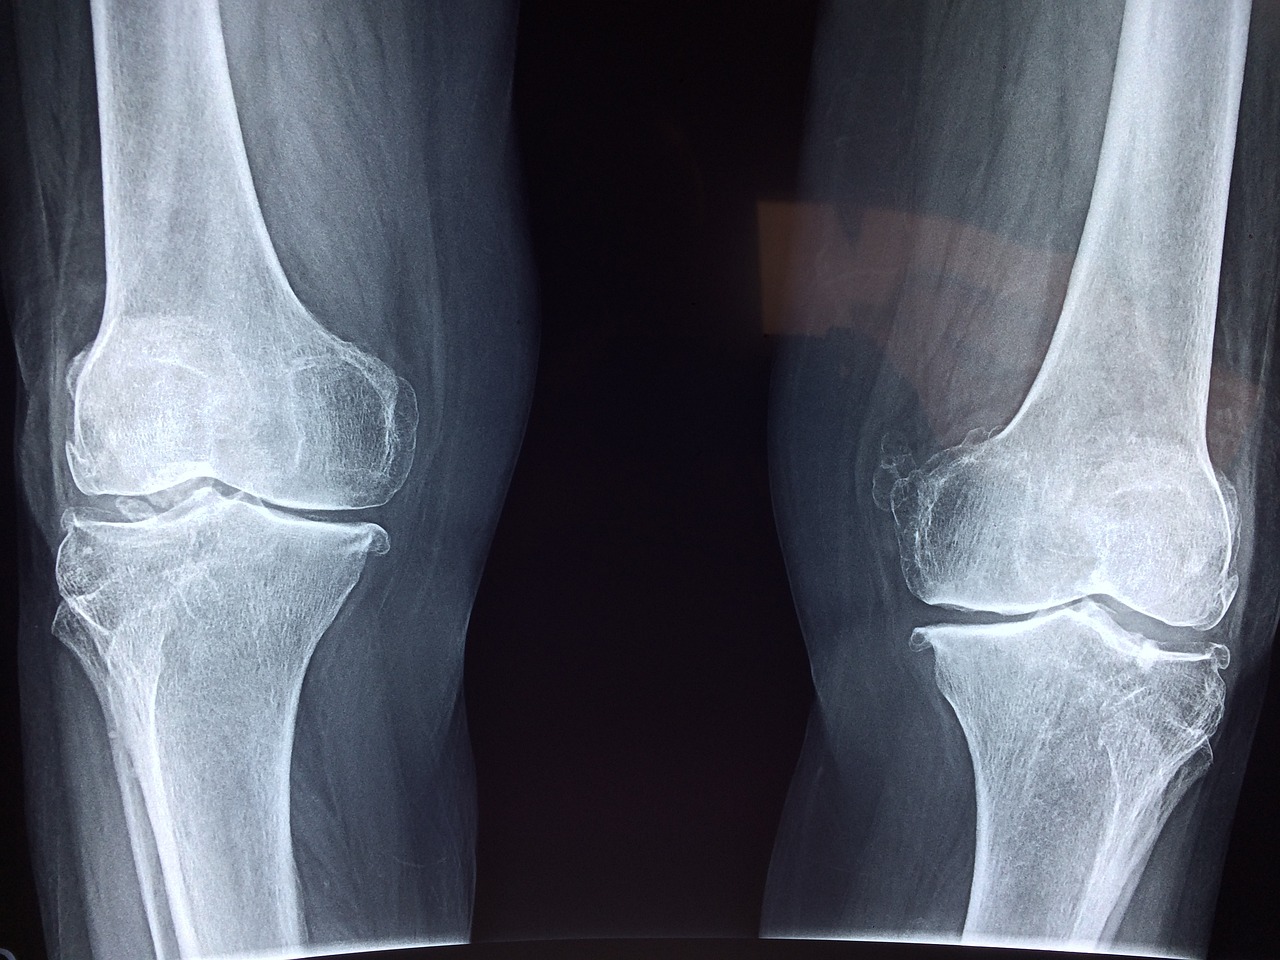

관절을 보호하고 있는 연골의 손상이나 퇴행성 변화로 인해 관절을 이루는 뼈와 인대 등에 손상이 생겨 염증과 통증이 발생하는 질환으로 관절 질환 중에서 가장 많이 발생하는 질환입니다.

6) 변형

시간이 지남에 따라 관절 모양이 변형될 수 있습니다.

손가락 관절염의 경우 손가락이 구부러지거나 굽어질 수 있습니다.

2) 수술적 치료

a. 관절경 수술

- 작은 절개를 통해 관절 내시경을 삽입하여 손상된 연골 조각을 제거하거나 수리하는 방법입니다.

c. 관절 치환술

- 손상된 관절을 인공 관절로 대체하는 수술이며 무릎, 엉덩이, 어깨 등의 관절에 주로 시행됩니다.